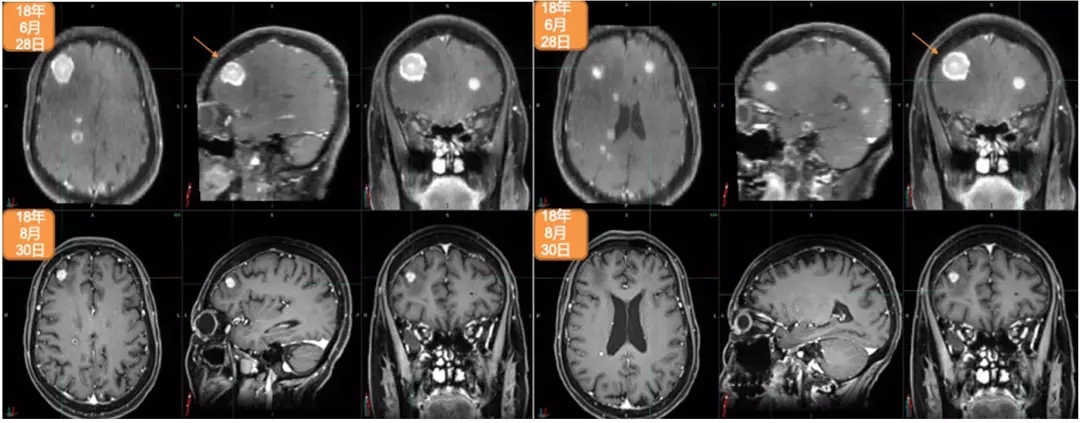

Nocturne GmbH:人工智能技术视网膜分析支持脑疾病诊断决策系统(德国)

夜曲有限公司